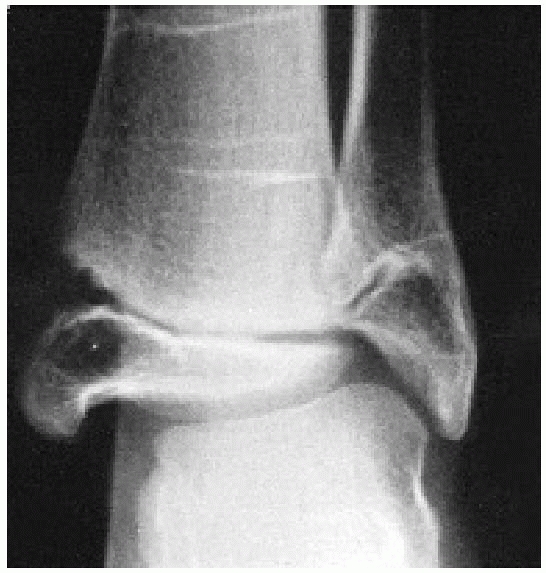

![]() |

|

FIGURE 26-36 A. Anteroposterior view of a patient with a pronation-eversion external rotation fracture. B. Postreduction view shows residual gapping of physis suggesting periosteal interposition. C. Anteroposterior view obtained for a new injury (medial malleolar fracture) shows premature closure of the physis.